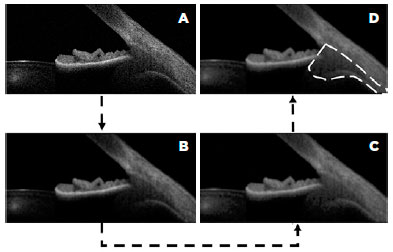

Image J software was used to measure the area of the ciliary muscle in each image (Figure 1A-D). The original image was converted into an 8-bit image (Figure 1A). Then the whole image was smoothed (Figure 1B), and the contrast was enhanced with a nonlinear histogram equalization (Figure 1C) to highlight different areas and borders. Then, the observer roughly delimited the area of the anterior ciliary muscle using two lines. One line was along the border between the sclera and the ciliary muscle, while the other line went through the scleral spur and was perpendicular to the first line. An automatic selecting tool was applied to select the area of the anterior ciliary muscle (Figure 1D), and the area was calculated. Figure 2 shows a representative example of the area of interest of the anterior ciliary muscle section.